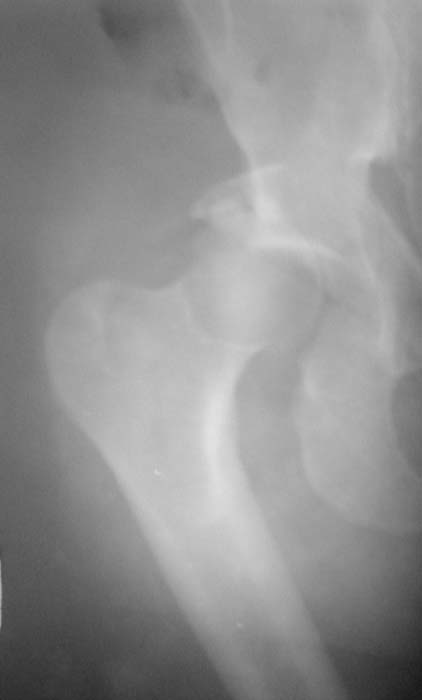

Уважаемые коллеги!Мужчина, 40 лет. Травма несколько месяцев назад. Получил закрытый вывих правого тазобедренного сустава и перелом вертлужной впадины (сним.1).Лечился скелетным вытяжением. Сейчас (сним.2) жалобы на боли, ограничение движений. Вопрос: тактика лечения (эндопротезирование и/или восстановительная операция, иное)?С уважением,А.В.Владзимирский

Вывих, похоже, вообще не был устранен. Или из-за дефекта заднего края сразу рецидивировал.

Для уточнения величины дефекта задней стенки и состояния головки необходима КТ. Если МРТ доступна, то и ее.